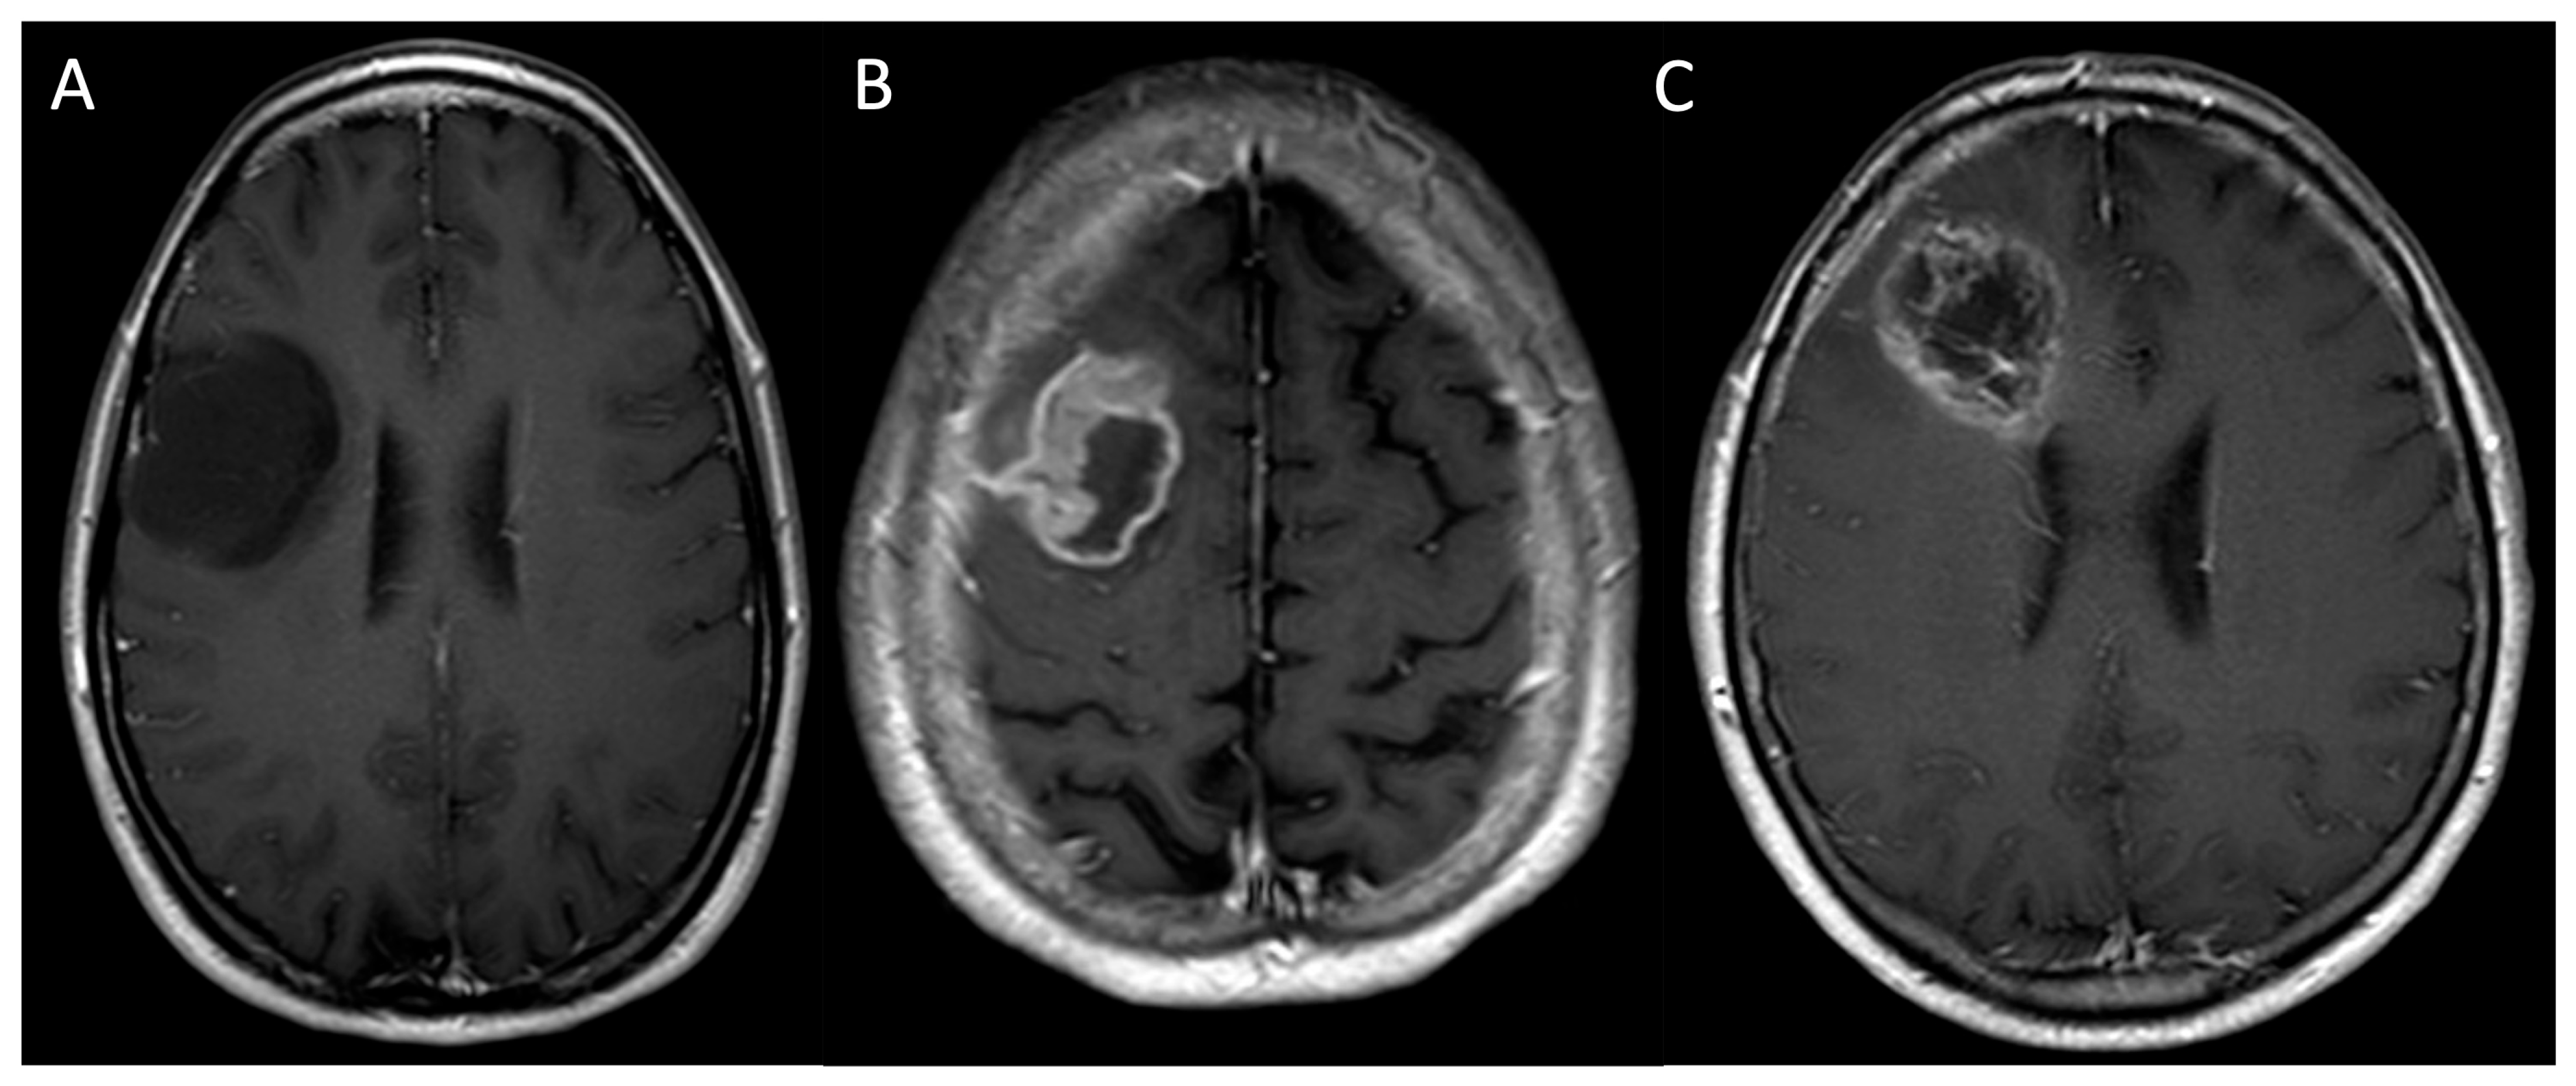

- Finck, T.; Gempt, J.; Zimmer, C.; Kirschke, J.S.; Sollmann, N. MR Imaging by 3D T1-Weighted Black Blood Sequences May Improve Delineation of Therapy-Naive High-Grade Gliomas. Eur. Radiol. 2021, 31, 2312–2320. [Google Scholar] [CrossRef]

- Kammer, N.N.; Coppenrath, E.; Treitl, K.M.; Kooijman, H.; Dietrich, O.; Saam, T. Comparison of Contrast-Enhanced Modified T1-Weighted 3D TSE Black-Blood and 3D MP-RAGE Sequences for the Detection of Cerebral Metastases and Brain Tumours. Eur. Radiol. 2016, 26, 1818–1825. [Google Scholar] [CrossRef]